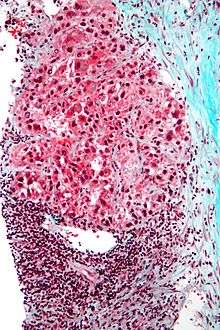

| Hepatocellular carcinoma in an individual who was hepatitis C positive. Autopsy specimen. | |

Microscopically, there are four architectural and cytological types (patterns) of hepatocellular carcinoma: fibrolamellar, pseudoglandular (adenoid), pleomorphic (giant cell) and clear cell. In well differentiated forms, tumor cells resemble hepatocytes, form trabeculae, cords and nests, and may contain bile pigment in cytoplasm. In poorly differentiated forms, malignant epithelial cells are discohesive, pleomorphic, anaplastic, giant. The tumor has a scant stroma and central necrosis because of the poor vascularization.[28]